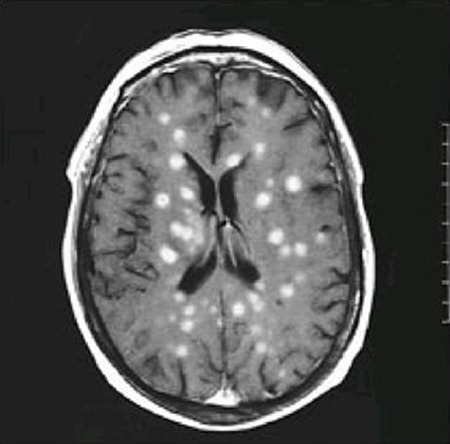

A 55-year-old kidney-transplant recipient presented with headache and fever. The cerebrospinal fluid contained 84 percent neutrophils. What is the most likely diagnosis?

Nocardia asteroides infection

Cerebral toxoplasmosis

Listeria moncytogenes infection

Miliary tuberculosis

Cryptococcus neoformans infection